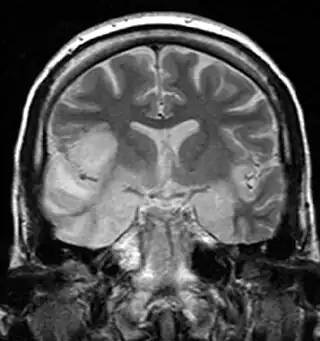

![]() Una IRM muestra una señal alta en los lóbulos temporales y la circunvolución frontal inferior derecha en un caso de encefalitis por HSV. | ||